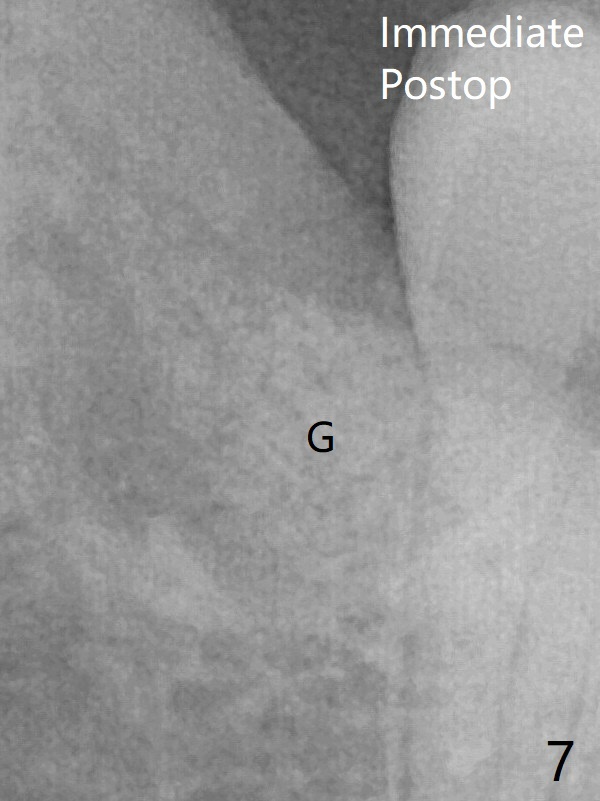

The transverse cortex connecting to the lamina dura (Fig.5 *) is obliterated when allograft is placed (Fig.7 G). The part of the graft remains in place 1 month postop (Fig.9) in spite of wound dehiscence (Fig.8). The bone graft loss is indicated by the fact of the reappearance of the transverse cortex (Fig.9).